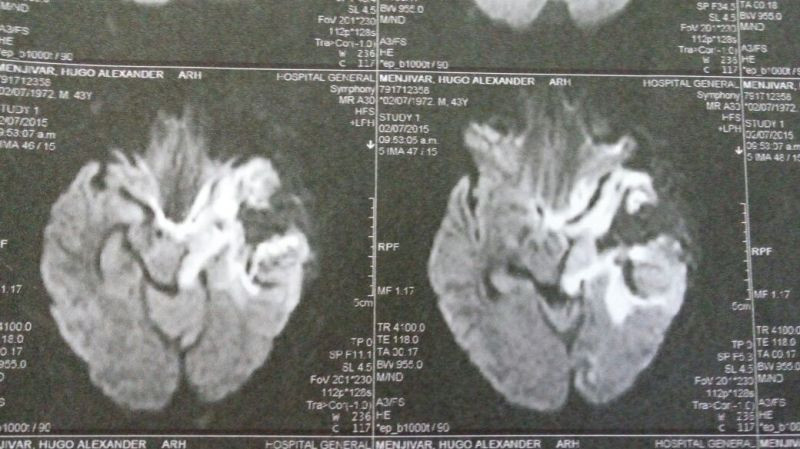

Oligodendroglioma temporal izquierdo Imagenes MRI Preoperatorio

Oligodendroglioma temporal Imagenes MRI Preoperatorio